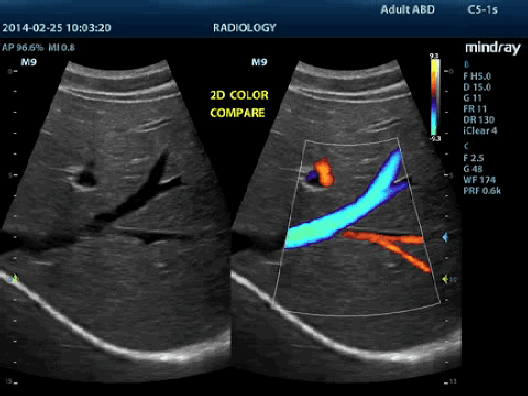

Визуализация с применением контрастных веществ UWN+ (нелинейная визуализация в ультрашироком диапазоне)

Самое большое преимущество УЗ-сканера M9T заключается в поддержке запатентованной Mindray технологии, позволяющей расширить возможности визуализации с применением контраста. Технология UWN+ дает возможность M9T обнаруживать и использовать как вторичные гармоники, так и нелинейные первичные сигналы, создавая изображения более высокого качества.

- Более высокая чувствительность к второстепенным сигналам, меньший расход действующего вещества

- Более длительное время действия активного вещества и более низкие требования к интервалу измерения

- PSHI™ (гармоническая визуализация с фазовым сдвигом)

Изолированная гармоническая визуализация для улучшения контрастного разрешения, обеспечивающая более четкое изображение с превосходным пространственным разрешением и меньшим уровнем шума.